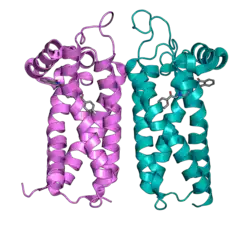

Although the sigma-2 receptor was identified as a separate pharmacological entity from the sigma-1 receptor in 1990,[6] the gene that codes for the receptor was identified as TMEM97 only in 2017.[7] TMEM97 was shown to regulate the cholesterol transporter NPC1 and to be involved in cholesterol homeostasis. The sigma-2 receptor is a four-pass transmembrane protein located in the endoplasmic reticulum. It has been found to play a role in both hormone signaling and calcium signaling, in neuronal signaling, in cell proliferation and death, and in binding of antipsychotics.[8]

The sigma-2 receptor takes part in a number of normal-function roles, including cell proliferation, autophagy,[11] cholesterol homeostasis,[12] and both non-neuronal and neuronal signaling. Much of sigma-2 receptor function relies on signaling cascades. The receptor's interaction with EGFR and PGRMC1 proteins allow for sigma-2 receptors to play diverse roles within cell through Ras, PLC, and PI3K signaling.